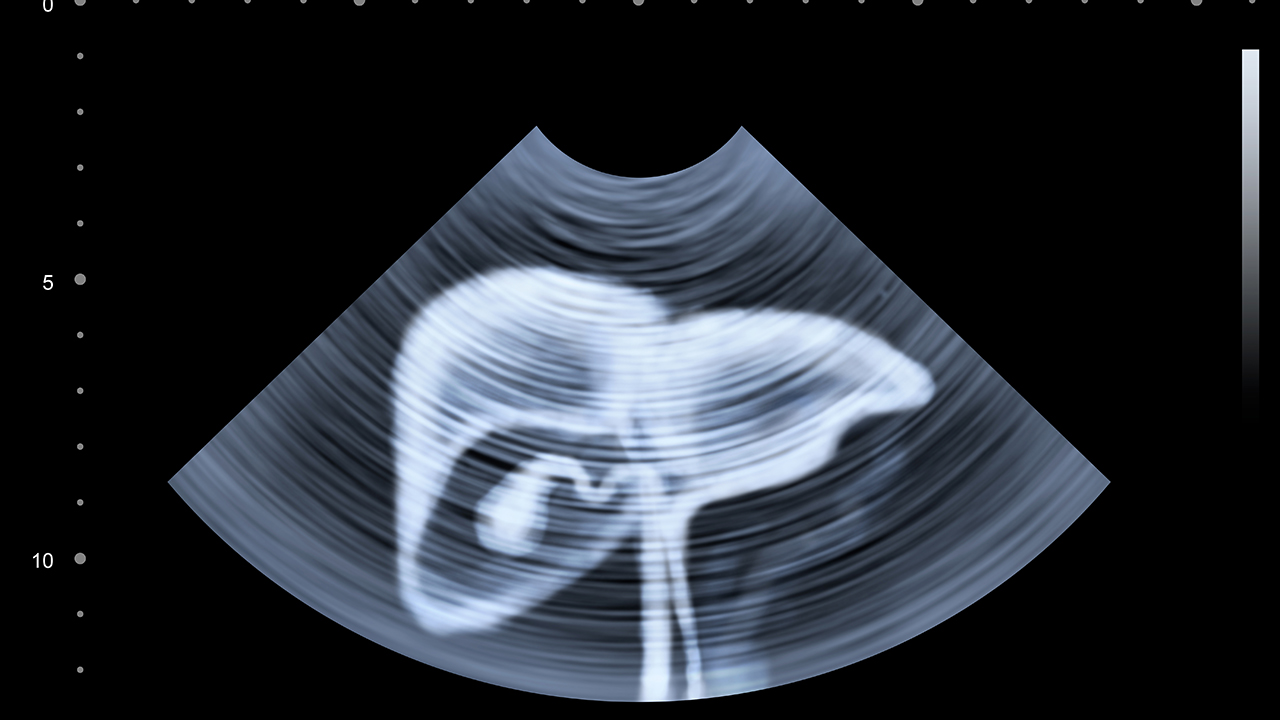

山东省立医院是山东省规模大的综合性医院之一,拥有的医疗设备和专业的肝癌诊疗团队。医院肝胆外科在肝癌手术、介入治疗和综合治疗方面积累了丰富的经验,能够为患者提供个性化的治疗方案。医院还配备了的影像诊断设备,能够早期发现肝癌病灶,提高治果。此外,医院在肝癌的多学科协作诊疗模式上也处于地位,能够为患者提供全方位的医疗服务。

山东大学齐鲁医院作为山东省的医疗机构,在肝癌治疗领域具有显著优势。医院肝胆外科和肿瘤中心在肝癌的手术治疗、射频消融、靶向治疗和免疫治疗等方面技术成熟。医院还设有肝癌多学科会诊中心,能够为患者制定优化的治疗方案。齐鲁医院在肝癌的基础研究和临床转化方面也取得了多项成果,为患者提供了更多治疗选择。

山东省肿瘤医院是山东省的三级甲等肿瘤专科医院,在肝癌的诊疗方面具有专业优势。医院拥有专门的肝胆肿瘤科,配备了的放疗设备和介入治疗设备,能够开展肝癌的放疗、介入栓塞等多种治疗方式。医院还注重肝癌的早期筛查和诊断,能够为患者提供从预防到治疗的全流程服务。在肝癌的综合治疗和个体化治疗方面,医院积累了丰富的临床经验。